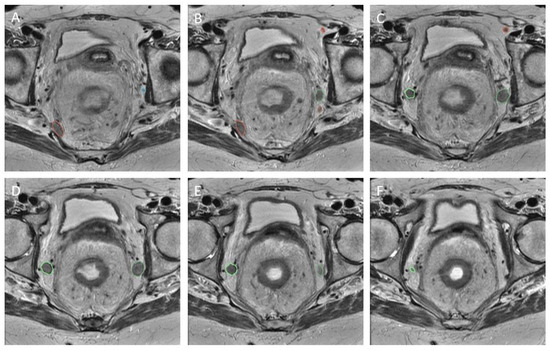

3.4. Explainability

In order to test the explainability of the models, three examples from the test set were chosen in which the model was confident of a positive recurrence, unsure of the presence of a recurrence, and was confident no recurrence was present. These are depicted in Figure 7 along with the confidence values of the model. The results of the explainability methods described previously are shown in Figure 8. The corresponding SSIM and MSE values are provided in Table 4. Good agreement can be seen between the GradCAM, XGradCAM, and EigenCAM methods, with SSIM values ranging from 0.772–0.930 for these methods. The corresponding MSE values were found to be between 0.024 and 0.003. The saliency and FullGrad methods were found to show significantly less agreement. This is likely due to the pixel-based mapping for the case of saliency. For the case of FullGrad, the sum of gradients of all biases appeared to saturate the image.

Figure 7.

Three examples of an input data point corresponding to a positive recurrence with high confidence (top row), positive recurrence with low confidence (middle row), and no predicted recurrence with high confidence (bottom row). The left column depicts the node before treatment, the middle column after treatment, and the right column the manual delineation. Overlaid also are the predicted probabilities of recurrence provided by the deep learning model.

Figure 8.

Comparison of the various explainability methods as defined in the text. Each method was applied to the three example cases of Figure 7. Each image was created by first plotting the post-treatment channel with the corresponding local attribution values subsequently added with fifty percent transparency.